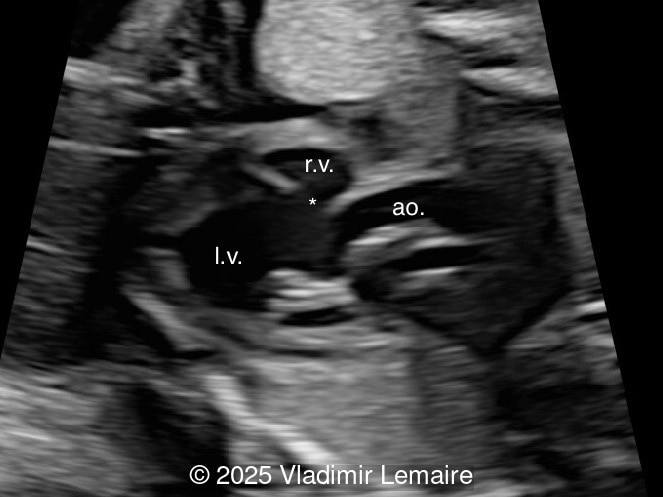

We present a case of isolated tricuspid atresia type 1 with persistent left superior vena cava. No other extracardiac anomalies were found. Our diagnosis was confirmed after birth.

In the images below, the abbreviations are as follows: RA: right atrium; RV: right ventricle; LV: left ventricle; MV: mitral valve; LA: left atrium; FO: foramen ovale; SVC: superior vena cava; LSVC: left superior vena cava; PV: pulmonary veins; PA: pulmonary artery; MPA: main pulmonary artery; RPA: right pulmonary artery; AO: aorta; dAO: descending aorta; aAO: ascending aorta; DA: ductus arteriosus; T: trachea; * marks the ventricular septal defect.

Tricuspid atresia is a rare anomaly, with an incidence of 0.08 per 1,000 live births, and is characterized by the lack of communication between the right atrium and ventricle. As a result, the right ventricle is hypoplastic. The tricuspid valve apparatus does not develop in the majority of cases, and the right atrioventricular junction appears as echogenic thickened tissue on ultrasound examination. An inlet type ventricular septal defect is always present, and the size of the right ventricle depends on the size of the ventricular septal defect. As a consequence of the obstructed tricuspid valve, a large interatrial communication, in the form of a widely patent foramen ovale or atrial septal defect, is necessary.

The four-chamber view in tricuspid atresia is diagnostic. It reveals a small right ventricle, a ventricular septal defect, and the absence of a right-sided atrioventricular junction. The size of the right ventricle mainly depends on the size of the ventricular septal defect: the smaller the ventricular septal defect, the smaller the right ventricle. Its contractility is normal with no myocardial thickening. The atretic tricuspid valve appears as echogenic thickened tissue and the right atrium is slightly dilated. The interatrial communication is large and there is often a redundant flap of the septum secundum that bulges into the left atrium. The interatrial and interventricular septa are malaligned.